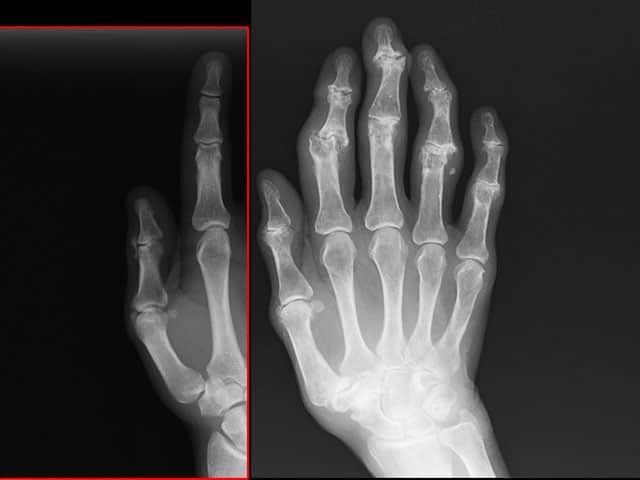

X-ray of Heberden and Bouchard nodes

A Heberden node describes a bony swelling of the distal interphalangeal finger joint. It is a sign of osteoarthritis, a degenerative joint disease.

A Bouchard node is a similar swelling affecting the proximal interphalangeal finger joint [1].

A Heberden node is a bony swelling of a distal interphalangeal joint and a Bouchard node is a bony swelling of the proximal interphalangeal joint.